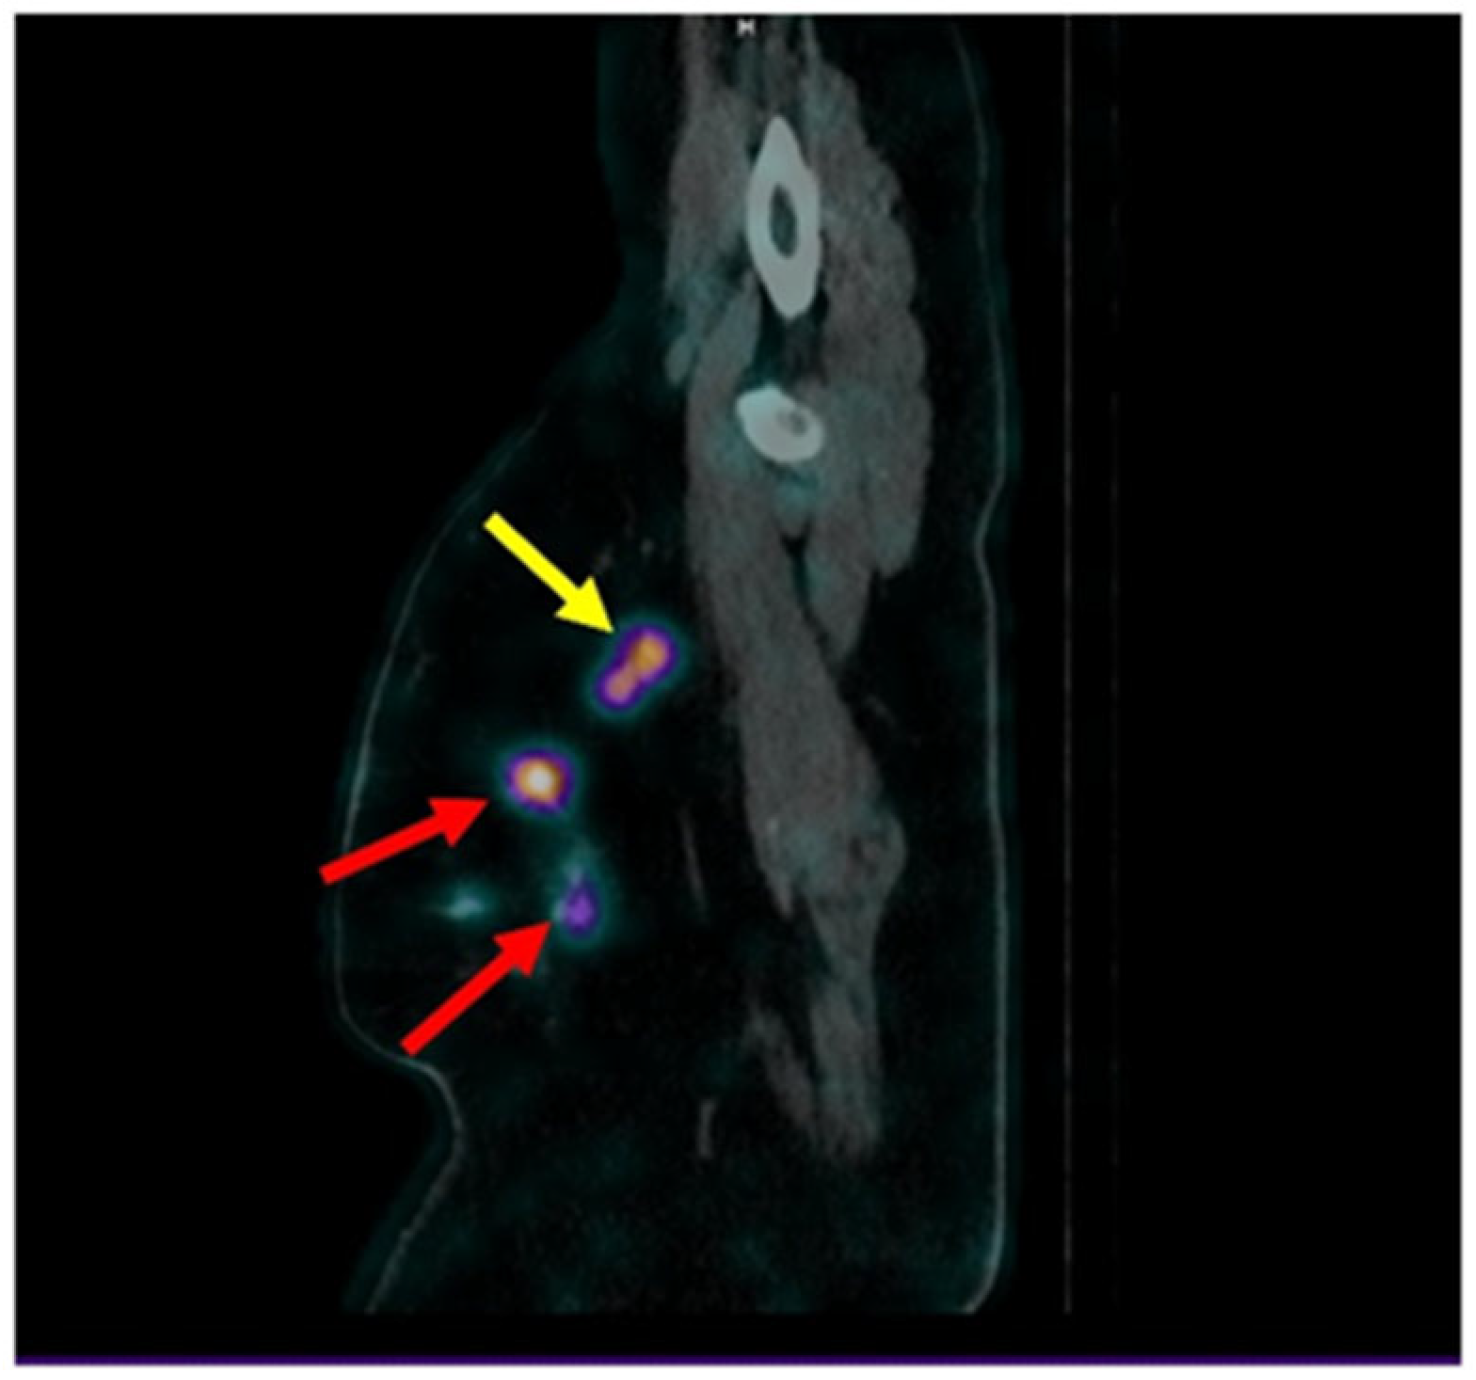

3. Results